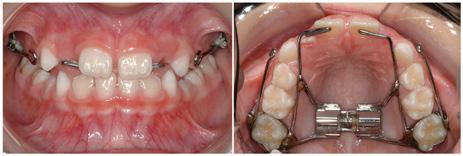

Photographs (Figure 7) were obtained at the age of 8 after one year of treatment. A lateral cephalogram, its tracing and the cephalometric values (Figure 8a and Figure 8b) were also obtained at the same time. The pre-treatment/posttreatment superimposition (Figure 9) reveals that correction occurred both dentally and skeletally. The maxilla and maxillary dentition moved slightly forward. The additional extrusion of the maxillary molar resulted in bite opening and downward and backward jaw rotation. Fortunately, this is something this patient could tolerate. Bottom line, it is better to open the bite in a patient who is Class III and deep than Class III and open.

Photographs (Figure 10) obtained at age 10, two years later, show that the overjet correction remained stable. I completed comprehensive orthodontic treatment on this patient’s older sister four years later. So, at age 14, I know with certainty that the patient described in this case report remained stable through adolescence. The family never chose to do any additional orthodontic treatment.